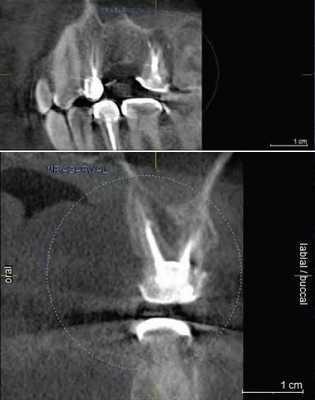

В периапикальной области обоих корней определялся обширный сливной очаг деструкции кости протяженностью 11х6 мм, который распространялся до кортикальной выстилки нижней челюсти канала с ее локальным разрушением (рис. 6) .

Рис. 6. КЛКТ, МПР. Прицельная визуализация апикальных очагов деструкции в обл. 4.7 зуба.

После уточнения анатомо-топографических особенностей системы корневого канала было проведено дальнейшее повторное эндодонтическое лечение зуба 4.7 с инструментальной обработкой 5 каналов, ирригацией 3%-ным раствором гипохлорита натрия, временным пломбированием каналов гидроокисью кальция ( Calasept ) на 2 надели. Каналы запломбированы гуттаперчей с эпоксидным силлером, коронковая часть восстановлена постоянной реставрацией.